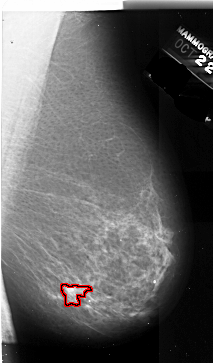

A_1008_1.RIGHT_CC

FILE: A_1008_1.RIGHT_CC.OVERLAY

TOTAL_ABNORMALITIES 1

ABNORMALITY 1

LESION_TYPE MASS SHAPE IRREGULAR MARGINS ILL_DEFINED

ASSESSMENT 4

SUBTLETY 4

PATHOLOGY MALIGNANT

TOTAL_OUTLINES 1

BOUNDARY